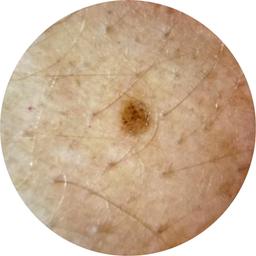

ISIC_1970657

Information

2451 x 2451

MEL-SELF Trial, https://www.sydney.edu.au/medicine-health/our-research/research-centres/melself-project.html

acquisition_day 139

age_approx 55

anatom_site_1 Upper extremity

anatom_site_general upper extremity

concomitant_biopsy False

diagnosis_1 Benign

diagnosis_confirm_type single image expert consensus

family_hx_mm True

fitzpatrick_skin_type I

image_manipulation instrument only

image_type dermoscopic

lesion_id IL_5024300

patient_id IP_5414092

personal_hx_mm True

sex female